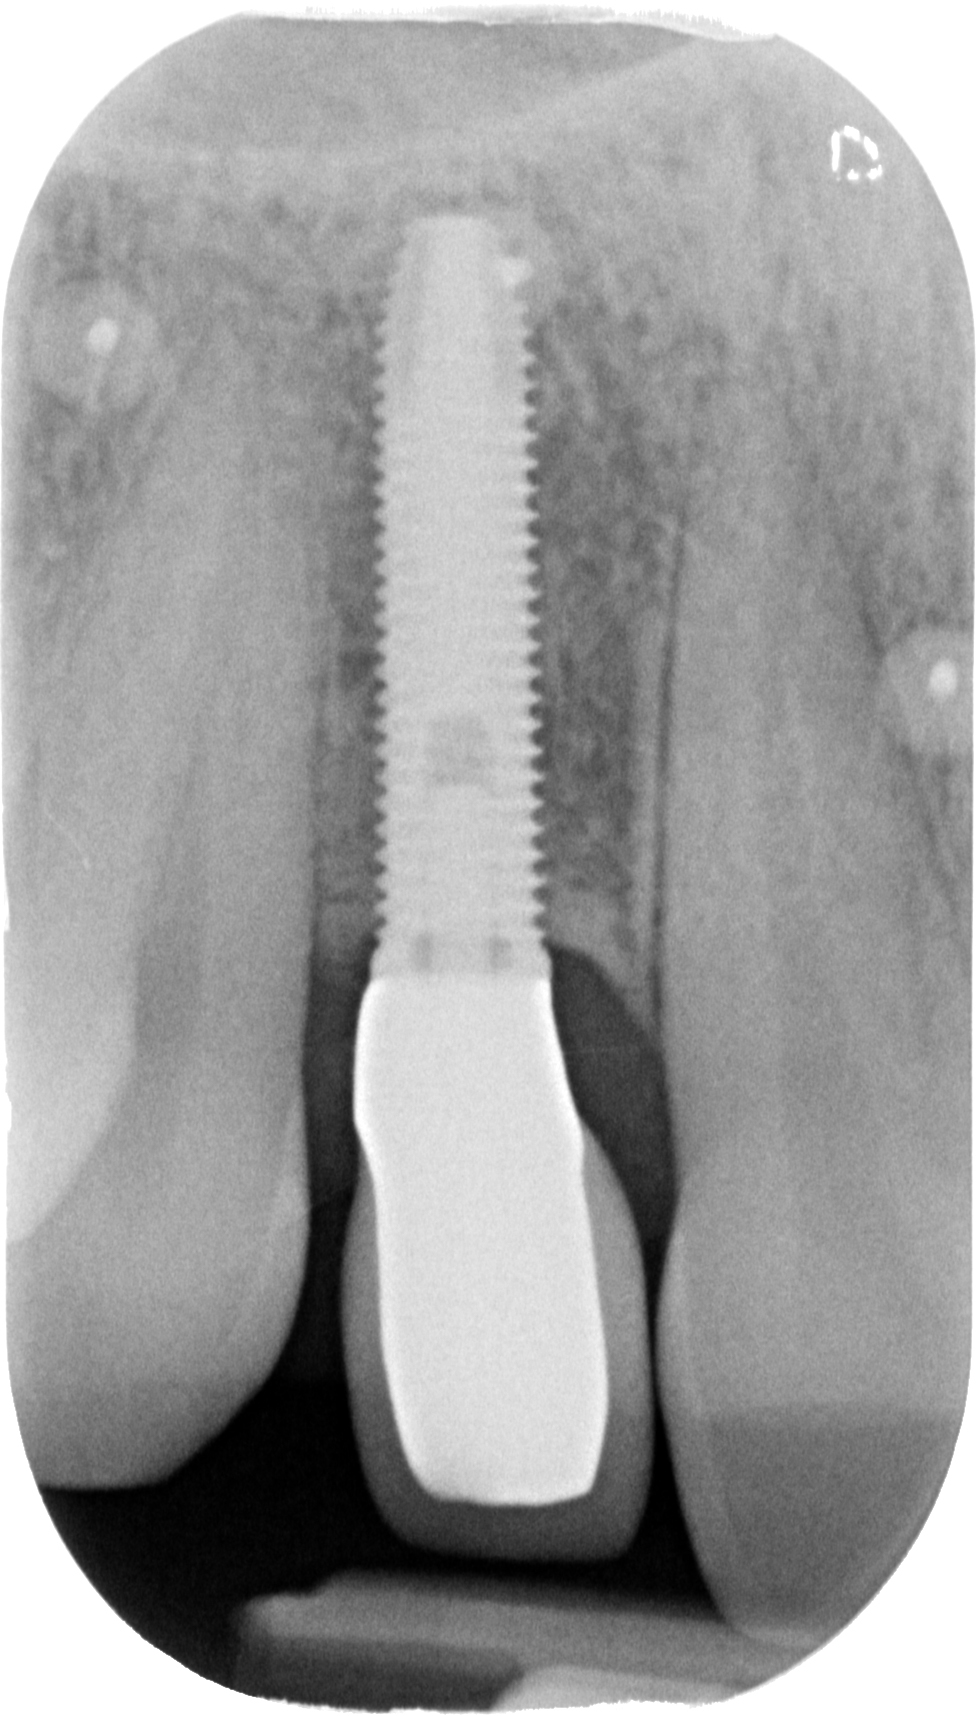

Prendiamo un caso quotidiano. Quello di Alessia che ha 33 anni:

Puoi buttare giù due viti e metterci sopra due denti facendo una cosa molto lontana dalla natura.

O puoi riabilitare la paziente adeguatamente:

Ma per fare questo non ci sono polverine magiche di osso di dinosauro o impianti di un millimetro. Ci sono anni di studio, sudore e sangue (E SGUARONE!!) per noi… e un VAS 2 per la paziente!!!!!!! ?